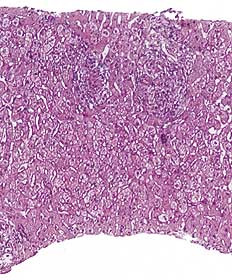

Pasient 3 . 30 år gammel kvinne. Hun fikk meningitt fire år gammel og fra tiårsalderen epilepsi. Det ble startet behandling med fenytoin, som pasienten brukte frem til hun var 22 år gammel. Man skiftet da til karbamazepin. Seks måneder senere ble hun innlagt i medisinsk avdeling. Hun hadde da vært ikterisk i seks dager, men var for øvrig uten allmennsymptomer. Resultatet av blodprøvene er vist i tabell 1. Det ble mistenkt medikamentell hepatitt, og karbamazepin ble seponert. ANA ble påvist svakt positiv, og ved serumelektroforese var det polyklonal økning i gammaregionen. Paul-Bunnells prøve og antistoffundersøkelse med hensyn på hepatitt A-virus og hepatitt B-virus var negative. Behandling med fenytoin ble gjenopptatt etter utskrivningen, men seks år senere ble fenytoin igjen seponert til fordel for karbamazepin på grunn av manglende anfallskontroll. 21 måneder etter dette ble hun så på nytt innlagt i medisinsk avdeling. I motsetning til første gang hadde hun nå følt seg slapp, kvalm og uvel i ti dager. Hun hadde anoreksi med gjentatte brekninger. Ved innkomst var hun afebril, BT 105/80 mm Hg og puls 64 regelmessig. Hun var i god allmenntilstand, men tydelig ikterisk, for øvrig var det intet påfallende ved klinisk undersøkelse. Blodprøver viste også denne gangen patologiske leververdier (tab 1). Karbamazepin ble igjen seponert, pasienten kom seg gradvis. Forløpet av blodprøvene er vist i figur 2. ANA var sterkt positiv, med en titer på 1 024 som var uforandret to måneder etter utskrivningen. IgG var forhøyet, med en verdi på 24,9 g/l (referanseområde: 6,9 – 15,7 g/l), og var fortsatt forhøyet ved kontroll to måneder senere, med en verdi på 23,6 g/ l. Verdiene for IgA og IgM var hele tiden normale. Leverbiopsi ble utført og viste akutt og kronisk betennelse med fibrose, tegn til nekrose av parenkymceller og kolestase. Ultralyd lever og galleveier viste mulig ødem i galleblæreveggen med omliggende fibrotiske forandringer, men ingen konkrementer. Antistoff mot hepatitt A-virus eller hepatitt B-virus ble ikke påvist, og det var normale verdier for ceruloplasmin og alfa-1-antitrypsin. 12 år senere viste nye blodprøver fortsatt forhøyet ANA, med en titer 256, og IgG-fraksjon i serum på 17,5 g/l.

Medikamentelle leverskader kan ut ifra biokjemiske parametere og histologi klassifiseres som parenkymatøse, kolestatiske eller som en kombinasjon av dette (1, 9). Ved gjennomgang av et stort antall rapporter om karbamazepinrelatert leverskade finner Stricker og medarbeidere alle disse formene representert (8). Vi fant at pasient 3 frembød et kolestatisk mønster, mens de to andre kan karakteriseres ved parenkymatøs leverskade. To av våre pasienter fikk påvist sterkt positiv ANA-titer, og en av dem hadde i tillegg forhøyet IgG-fraksjon i serum. Både ANA og andre autoantistoffer er blitt påvist i sammenheng med medikamentelle hepatitter (9, 10). Dette oppfattes som en aktivering av immunsystemet og at immunologiske mekanismer kan ha betydning for leverskader som er utløst av medikamenter. Hos våre pasienter ble ANA negativ (pasient 2) eller titer ble kraftig redusert (pasient 3) etter seponering av karbamazepin.